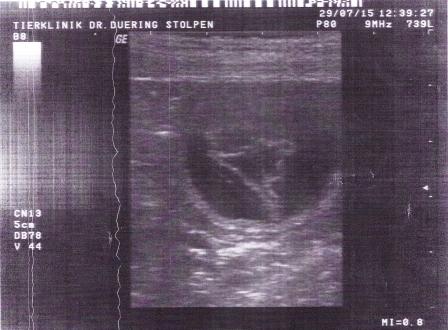

Am 29.07.2015 waren wir mit Lofty zum Ultraschall

- nun ist es Gewissheit Lofty bekommt Babys - unser B-Wurf steht bevor